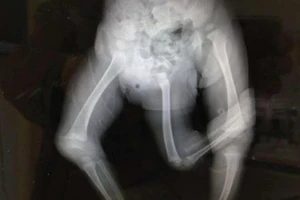

Kỳ lạ cậu bé sinh ra đã có 3 chân